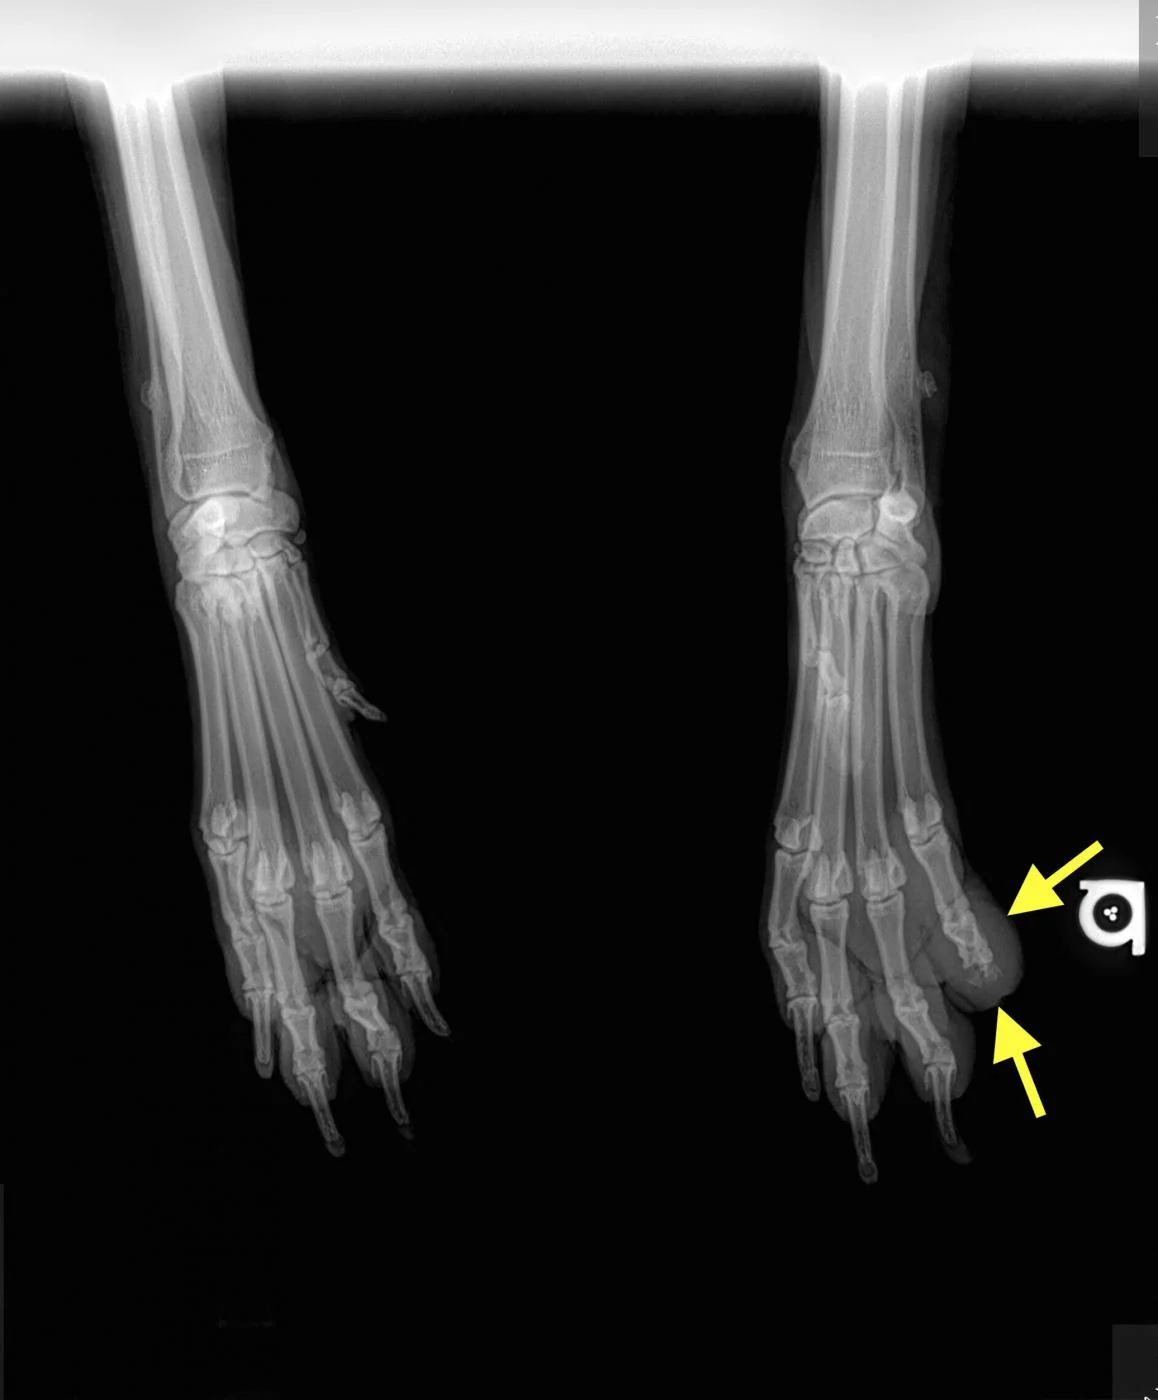

FIGURE 1

Digit melanoma

A single craniocaudal radiograph illustrates the forepaws of a 12-year-old neutered male Airedale terrier with digit melanoma. Moderate circumferential soft tissue swelling of the 5th digit of the left thoracic limb and significant lysis of the distal phalanx can be noted (arrows). The aggressive monostotic lesion of the distal phalanx of the 5th digit and associated soft tissue swelling are consistent with digital melanoma, which was confirmed via histopathology after digit amputation.